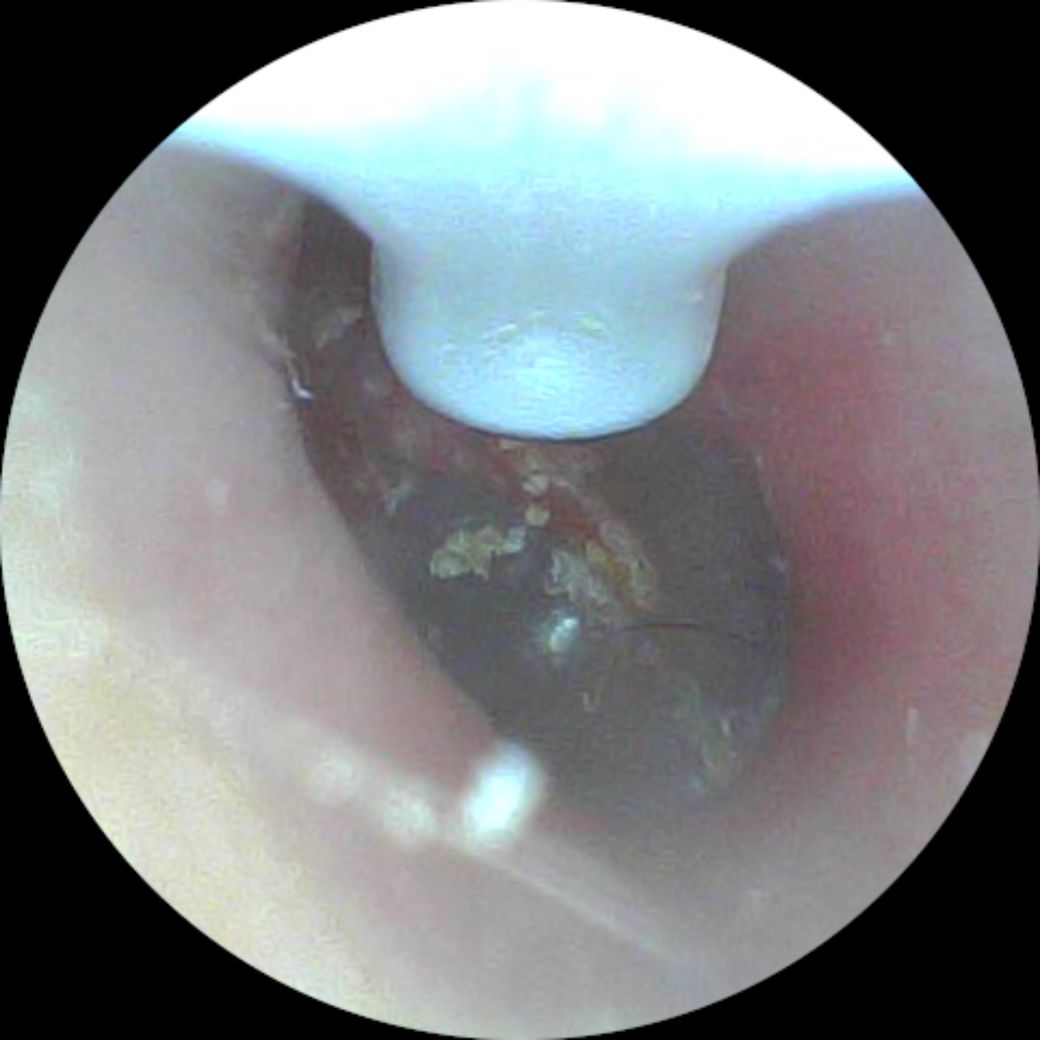

고막에 붙어 있는 귀지 뺄 수 있는 방법은 없나요

집에서 핸드폰 연결해서 귀지 팔 수 있는 귀이개 사용 중인데요 고막? 같은 막에 붙어있는지 너무 깊어서 귀이개가 잘 닫질 않고 아파서 근데 눈에 보이니 넘 거슬려요

이거 뺄 방법 없나요?

• 2번 째 사진

귀지가 고막에 붙어있는데 너무 깊어서 귀이개가 잘 닫지 않는데 눈에 거슬리시는 군요

고막에 붙어있으며 소량이네요

아마도 병원에 가서 떼달라고 해도 하지 않을 것입니다

위험하니 환자분도 아예 시도하지 마세요

고막 천공될 수 있습니다